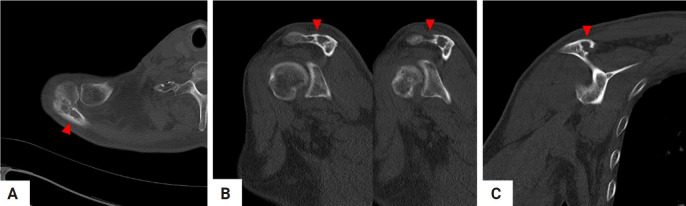

Epithelioid hemangioma of bone is a rare benign vascular tumor. Because of the locally destructive clinical presentation and the presence of atypical histologic features with increased mitotic activity and necrosis, it is often misdiagnosed as low-grade malignant epithelioid hemangioendothelioma or high-grade malignant epithelioid angiosarcoma. Correct diagnosis through imaging studies and histopathological examination is mandatory to determine the appropriate course of treatment, as the prognosis differs from that of other malignant hemangioma tumors. A 69-year-old male who presented with intractable shoulder pain caused by epithelioid hemangioma in the acromion of the scapula was treated with tumor curettage. This paper reports a good result with a review of the relevant literature.